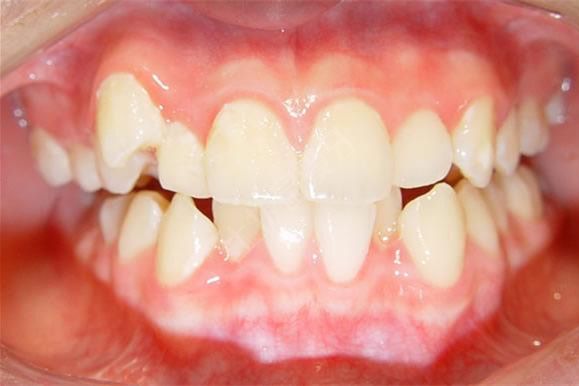

牙齒擁擠

一般牙齒不齊、擁擠,口腔內(nèi)空間已經(jīng)不夠用,這種情況是需要拔牙矯正的情況,首先會(huì)考慮拔除智齒或多生牙獲得—定空間進(jìn)行矯正,具體情況要看醫(yī)生怎么說(shuō),不過(guò)像牙齒擁擠改善前凸這種情況是你不拔智齒就無(wú)法做正畸的,可見(jiàn)智齒對(duì)牙齒正畸想象還是非常大的。